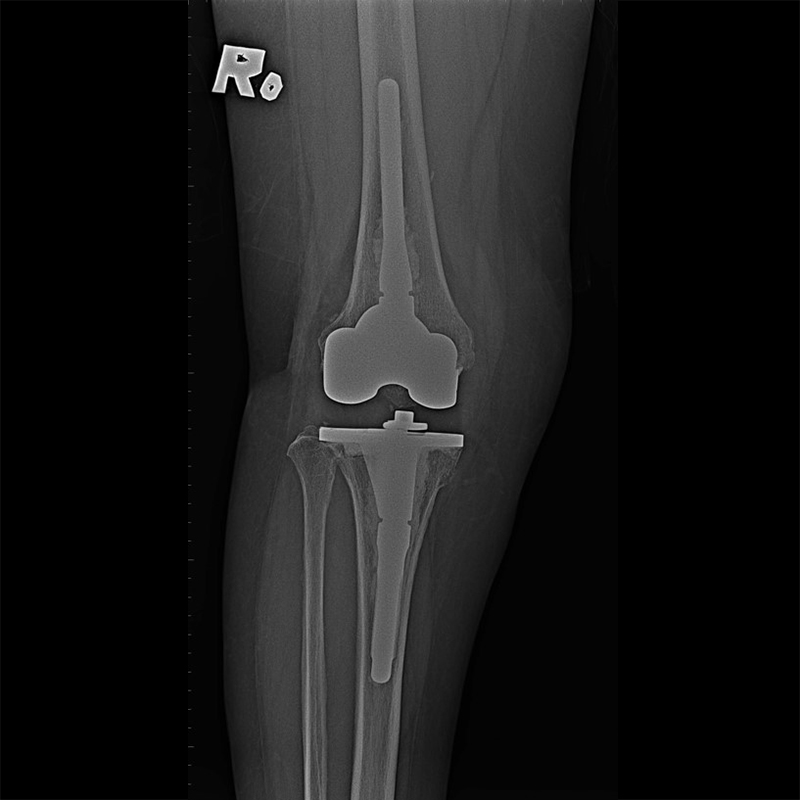

外院失敗本院再置換 首頁 案例分享 膝關節手術 外院失敗本院再置換 蕭女士 69歲 術前 術後 81歲 林女士 術前 術後 蕭女士 69歲 術前 術後 鄒女士 69歲 術前 術後 李女士 74歲 術前 術後 吳女士 71歲 術前 術後 謝女士 65歲 術前 術後